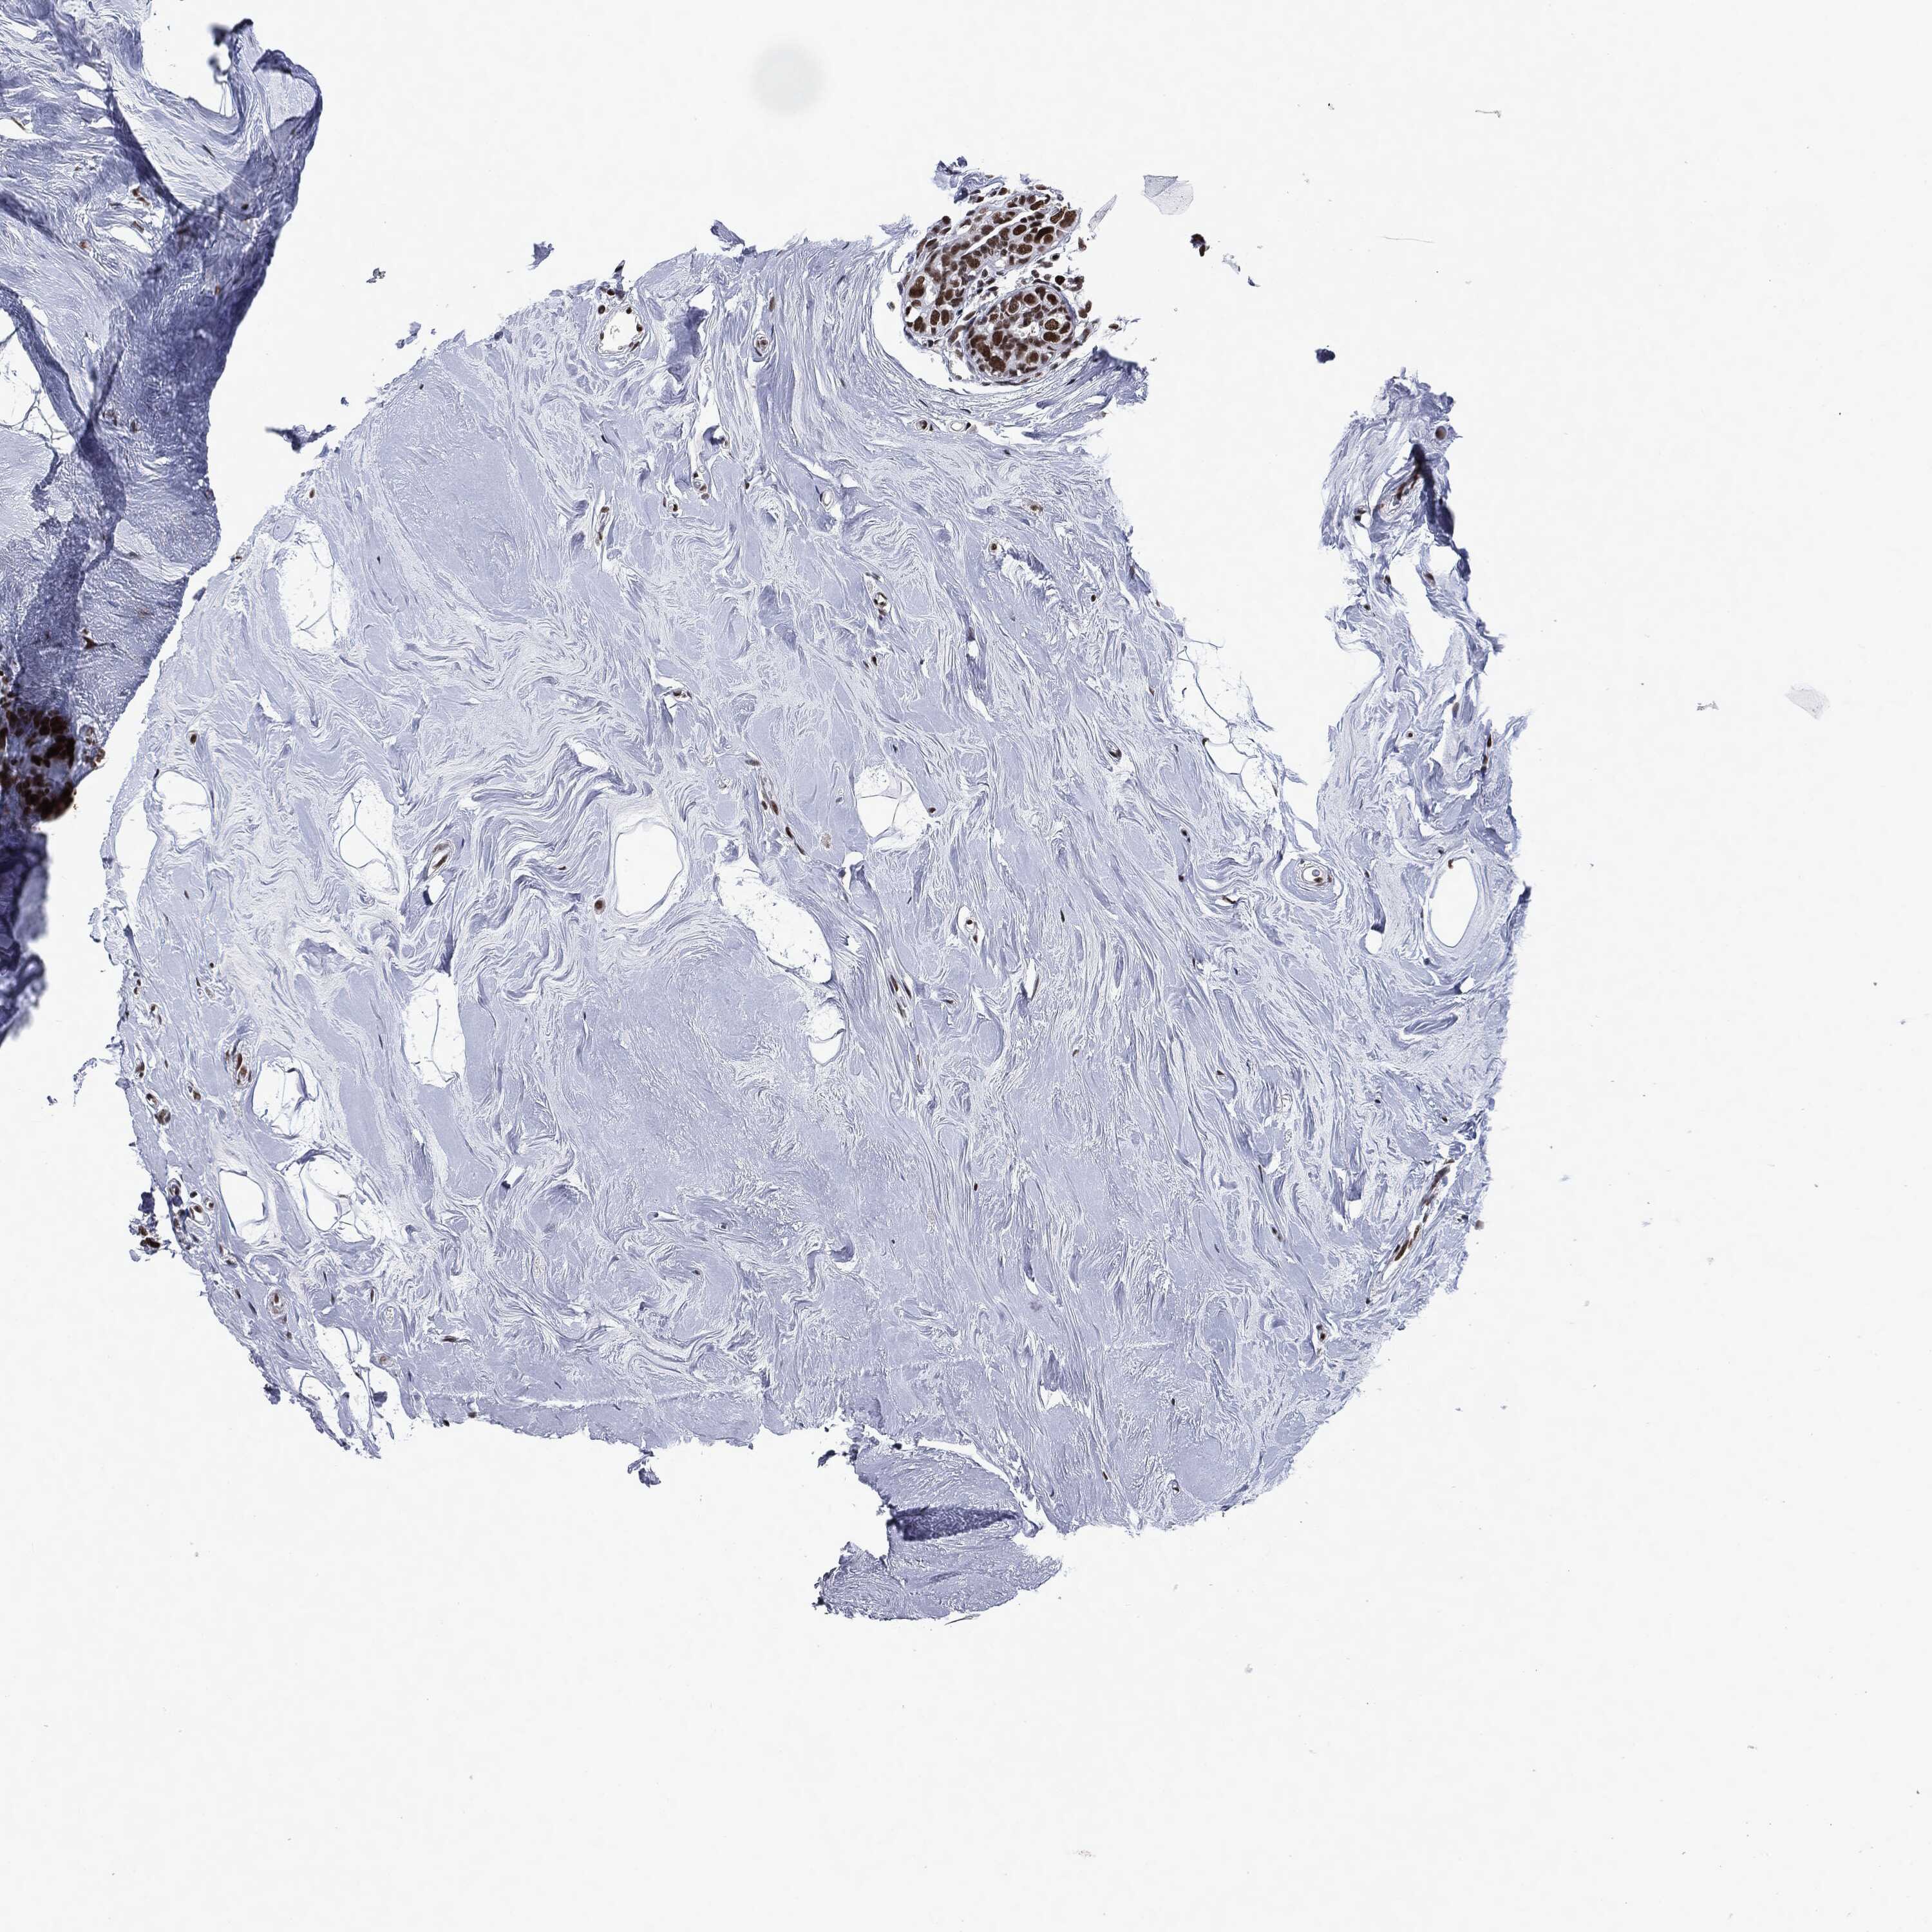

BRCA TCGA BRCA VALIDATION PROTEIN EXPRESSION

ANTIBODIES

AND

VALIDATION